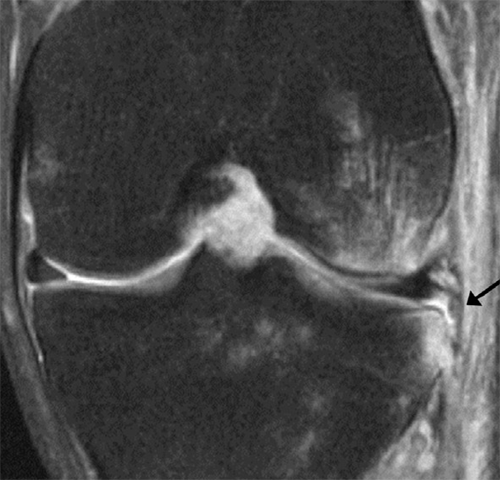

This article, published in Skeletal Radiology, we investigated feasibility of high resolution conventional MR, and quantitative novel MR, and biomechanical techniques to characterize pathology of h ...